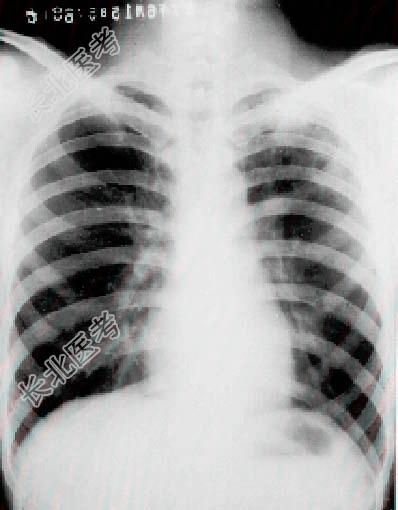

- [材料题] 患者男性,25岁。半年前因咳嗽.发热.胸痛,在当地诊断为肺炎,用青.链霉素治疗三周,一般情况好转停药。近数月又咳嗽.痰多,一直按肺炎治疗,后曾短期加抗痨药效果不佳,因诊断未明而入院。体检:左上肺呼吸音略低,胸片见下图。

- 多项选择题1.根据病史胸片,你认为下列那种病可能为大?